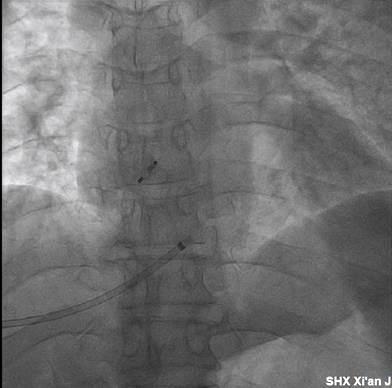

在做好周密的术前准备及应急预案后,4月6日下午17:30分,超声医学科魏炜教授凭借高超的技术与丰富的穿刺经验,在超声引导下对患者实施了精准肝静脉穿刺,整个穿刺过程快速、顺利、安全。

超声引导下肝静脉穿刺